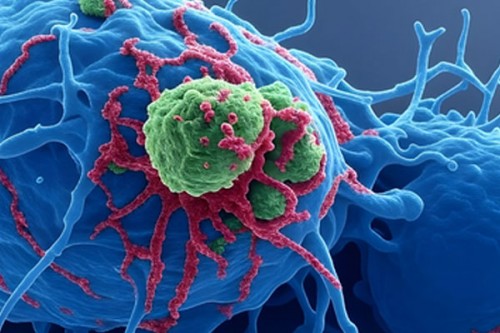

Hyaluronic acid may help improve gynaecological cancer treatment: Study

Technology | IANS | Published : Mon, Jan 19, 2026, 11:42 AM

Combining two medicines may help treat childhood brain cancer: Study

Technology | IANS | Published : Sat, Jan 17, 2026, 11:54 AM